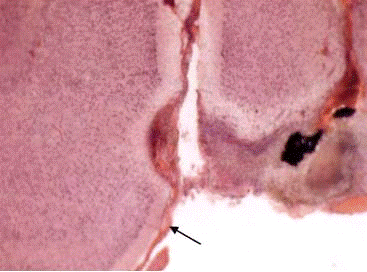

Моделирование последствий удаления невриномы VIII нерва заставляет нас обратить особое внимание на комплекс вестибулярных ядер, от которого начинается еще одна нисходящая система: вестибулоспинальный тракт. В этот комплекс входят следующие ядра: верхнее (Бехтерева), медиальное (Швальбе), нижнее (нисходящее), латеральное (Дейтерса) и группа x, y, z (Бродал с соавт., 1966). Нисходящий вестибулоспинальной тракт берет начало из латерального вестибулярного ядра (Дейтерса). Последнее имеет более тесные, чем другие вестибулярные ядра, связи со спинным мозгом. Окончания вестибулоспинальных нейронов обнаруживаются на интернейронах и мотонейронах VII-VIII пластин серого вещества спинного мозга. Следует отметить соматотопическую организацию вестибулоспинальной проекции. Повреждение ствола на уровне ядра Дейтерса с одной стороны приводит к нарушению позы животного. Это обусловлено нарушением взаимодействия мышц сгибателей и разгибателей, находящихся под контролем вестибулоспинального тракта (Бродал с соавт., 1966; Bacskai et al., 2002).